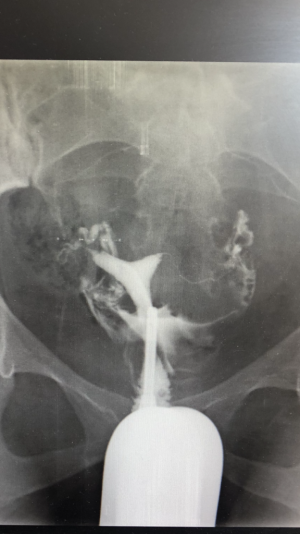

Rahim filmi çekildim,tüplerim açıkmış fakat rahim şekli için böyle yazılmış rapora. Arkuad uterus yani kalp şeklinde rahim. Burada iyi yorumlar da okudum,moral bozan yorumlar da. Acaba o yüzden mi olmadı 1 yıldır

Rahim filmi çekildim,tüplerim açıkmış fakat rahim şekli için böyle yazılmış rapora. Arkuad uterus yani kalp şeklinde rahim. Burada iyi yorumlar da okudum,moral bozan yorumlar da. Acaba o yüzden mi olmadı 1 yıldır